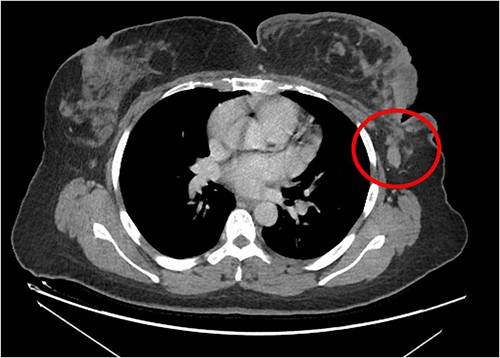

The patient was referred to medical oncology clinic. On exam, she had an eastern cooperative oncology group-performance status of zero, was in pain from her left breast. Assessment of the breast lump revealed a palpable, huge left breast mass, hard in consistency, around 10 cm in largest diameter. There were no palpable lymph nodes in the left axilla. Examination of the right breast was unremarkable. The affected breast is shown in Fig. 1. Otherwise, her chest and abdomen exam were unremarkable, with no lower limb edema. Baseline chest-abdomen–pelvis computed tomography (CT), shown in Fig. 2, showed a large left breast mass 8.0× 2.0 × 4.7 cm with diffuse skin thickening, few axillary lymph adenopathy, the largest of which measured 1.9 cm (shown in Fig. 3), with no distant metastasis. No magnetic resonance imaging was obtained prior to treatment as it was unavailable at the institute. The case was discussed by a multidisciplinary team of medical oncologists, radiation oncologists, surgical oncologists and pathologists. The final decision was that the patient should be treated as a case of high-grade sarcoma, so she was started on ifosfamide–adriamycin (IA) protocol (ifosfamide, 2500 mg/m2, mesna, 800 mg/m2 and doxorubicine, 75 mg/m2 intravenous (IV) for 3 days) as neoadjuvant, to be followed by surgery and adjuvant radiotherapy and chemotherapy. Paraffin blocks were requested by the pathologists for case revision at our institute.

Left breast mass along with involved axillary lymph nodes, encircled.

The patient received a total of six cycles of IA protocol, one cycle of goserelin as a means of fertility preservation, with remarkable clinical improvement, she stopped her morphine tablets (both long-duration and as needed) after the third cycle as her pain resolved, kept only on pregabalin. The mass shrunk remarkably as shown in Fig. 5.